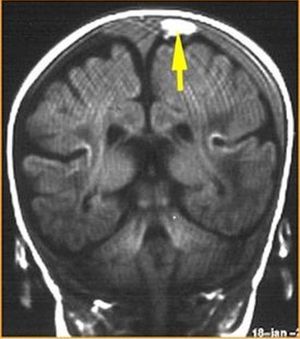

What is your diagnosis??

Subdural hematoma

Subdural hematoma.